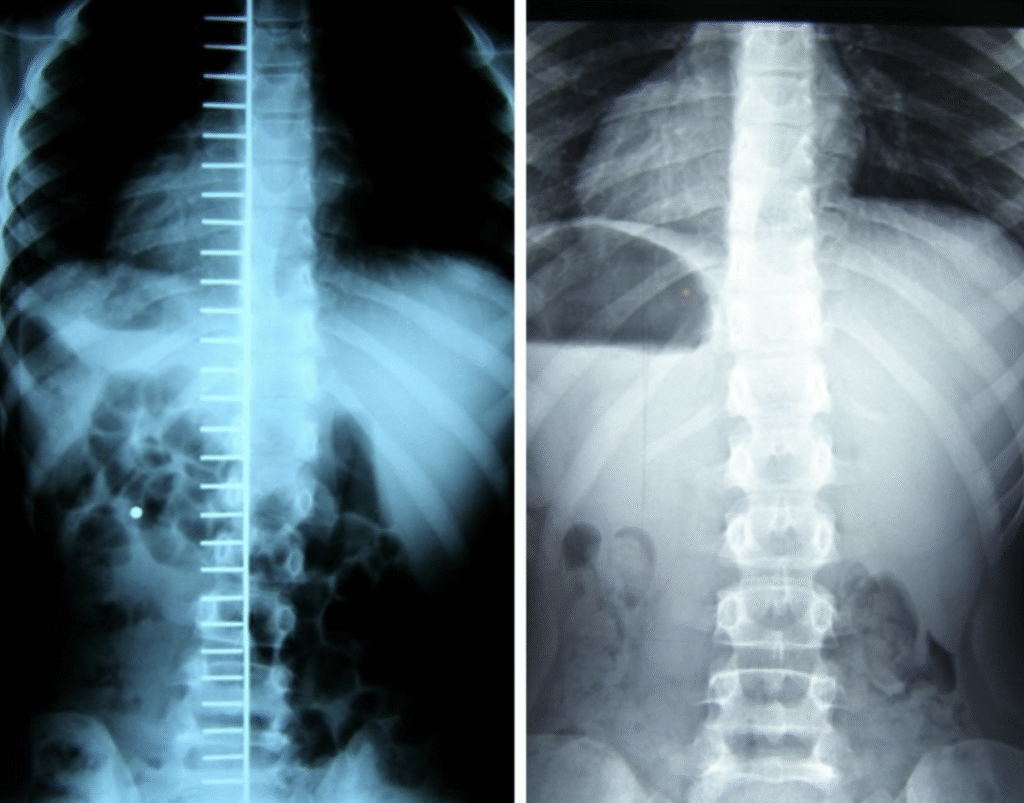

Maciej – 7 lat

Skolioza jednołukowa (statyczna) – zdj. z lewej. Korekcja uzyskana w trakcie jednej wizyty – zdj. z prawej